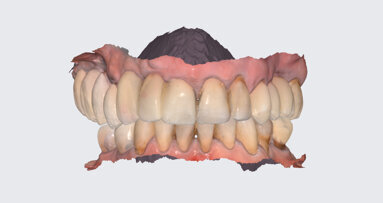

After 3 weeks of additional healing, fixture level impressions were accomplished for the laboratory phase. (Impregum 3M ESPE). The final single tooth implant-supported prosthesis can be seen in Figs. 10a & b. The post-insertion radiographic image at 14 months revealed excellent bone adaptation surrounding the implant, with sufficient interproximal height of bone (Fig. 11).

Placing dental implants in the maxillary anterior region requires precise planning, surgery, and prosthetic treatment. This article illustrated the steps needed to create ideal aesthetics in the maxillary anterior region. Rigorous treatment planning allows the implant surgeon, working with the restorative dentist, to select location, angulation, and spacing of dental implants to achieve ideal aesthetics. Treatment planning also dictates the necessity for hard- and soft-tissue grafting, which is often crucial for an ideal aesthetic result. Further, the prosthetic restoration of a dental implant must be ideal to achieve the desired aesthetic result. This article has discussed the importance of a comprehensive and interdisciplinary approach to treatment planning, surgery, and restoration of dental implants in the maxillary anterior region of the mouth.